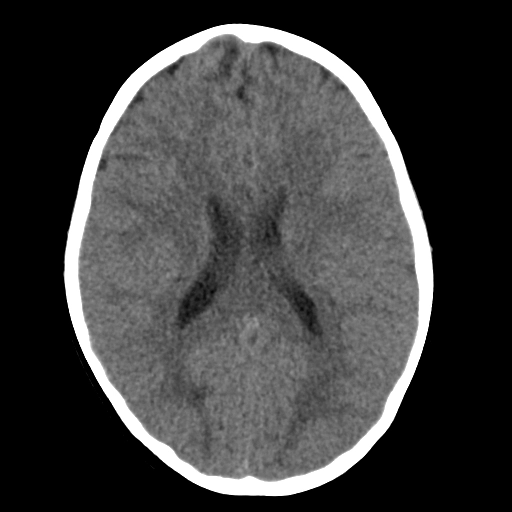

Di căn nhu mô não (Parenchymal metastases)